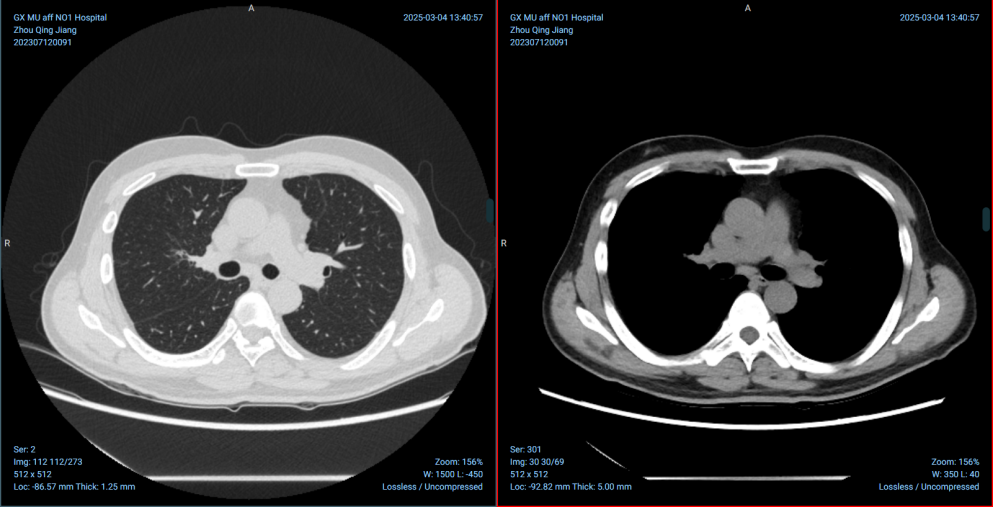

服药后肿瘤的变化,比我预想的要好的多,结果令人欣喜。按照医嘱,我在服药一个月后(2023年9月初)回到医院进行第一次复查。增强CT结果出来时,李主任告诉我:“效果非常好!肿瘤已经缩小了一大半,从4.2cm缩小到1.7cm!”

听到这个结果,我一下子有点懵,几乎不敢相信自己的耳朵。要知道,我确诊的是肺印戒细胞癌,这种类型相对少见且进展可能较快。没想到仅仅依靠每天口服一次药物(一次3片,每天一次),就能让肿瘤在这么短的时间内显著退缩!那一刻,压在心头的一块大石头仿佛被搬开了一些,我第一次真切地感受到:这场战斗,并非毫无胜算。虽然内心大大地松了口气,但我也非常清楚,这只是一个阶段性的胜利。李主任也强调,疗效显著说明药物有效,但必须坚持长期服药,并按时复查,不能掉以轻心。

时间转眼来到2025年7月。距离我开始服用伊鲁阿克已经将近两年。在这期间,我严格遵循医嘱,按时服药,定期复查(后期根据医生建议,稳定后多在当地医院复查,有问题及时线上沟通)。令人欣慰的是,我的肿瘤持续退缩,状态一直非常稳定。最近的复查结果显示,医生评估我已经达到了非常显著的部分缓解”(Partial Response, PR)——也就是有时医生会说的“大PR”。虽然不能算完全消失,但肿瘤已经缩得非常小,在影像上几乎看不出来新的问题,说明药物控制效果非常好

这个结果,连李主任团队都感到非常惊喜,伊鲁阿克的效果远远超出了预期——肿瘤不仅缩小了,更是基本上“消失”了,医生团队决定继续观察,密切随访。